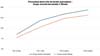

O volume médio de gordura enxertada foi de 116,7 mL no grupo de enxerto decantado e 123,3 mL no grupo de enxerto filtrado. A espessura média inicial do tecido subcutâneo era de aproximadamente 11 mm em ambos os grupos, aumentando para 22 mm no pós-operatório imediato no grupo decantado e 23 mm no grupo filtrado.

Houve reabsorção progressiva em ambos os grupos. A evolução da espessura subcutânea média em ambos os grupos está descrita na ►Tabela 1 e na ►Fig. 5.

No grupo enxerto decantado, a reducãomédia, comparando-se a espessura inicial apos lipoenxertia, foi de 9,90% no 15° dia, 19,27% no 1° mes, 23,59% no 3° mes e 26,36% no 6° mes. No grupo enxerto filtrado, a reducao media, comparando-se a espessura inicial apos lipoenxertia, foi de 7,74% no 15° dia, 14,85% no 1° mes, 20,67% no 3° mes e 22,80% no 6° mes. ►Fig. 6. A evolução ao ultrassom da espessura do tecido subcutâneo antes e depois da lipoenxertia pode ser vista nas ►Figs. 7-8. Os resultados de pré-e pós-operatório de uma paciente de cada um dos grupos estão exibidos nas ►Figs. 9-10.

A comparacao da reducao da espessura subcutanea em 6 meses entre as te cnicas de decantai; a o e filtrai; a o do enxerto na o mostrou diferenc a estatística significativa (p = 0,59).